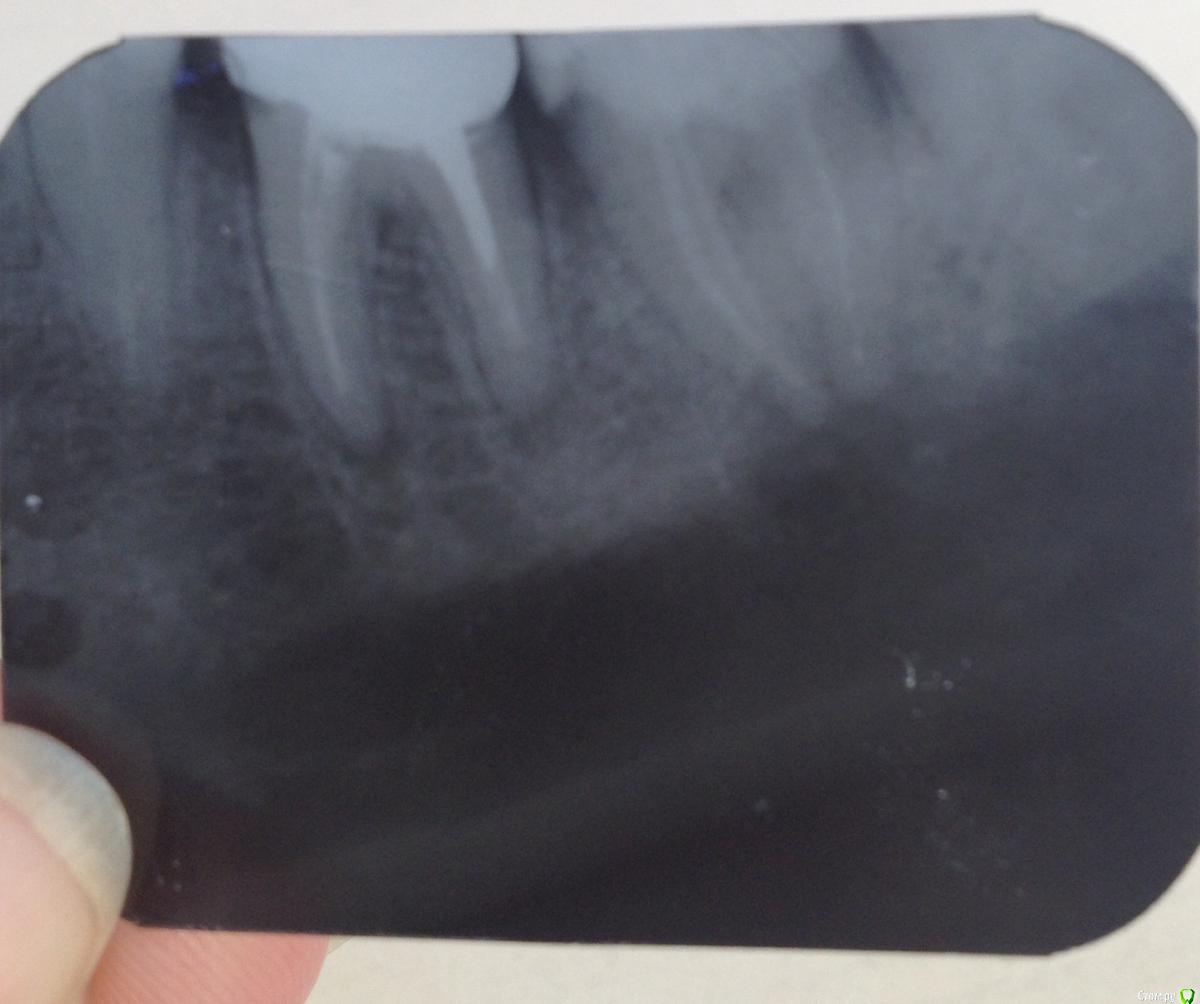

Тасечка Опубликовано 6 мая, 2015 Автор Поделиться Опубликовано 6 мая, 2015 Еще один снимок ,7 и рядом 6 ( на предыдущем 7 и 8) Ссылка на комментарий

Гарриевич Опубликовано 5 мая, 2016 Поделиться Опубликовано 5 мая, 2016 (изменено) заживление через 10 месяцевсоседа "перелечивал" не я к сожалению http://images.vfl.ru/ii/1462469714/80da6fa1/12556994_m.jpg Изменено 5 мая, 2016 пользователем Гарриевич 3 Ссылка на комментарий